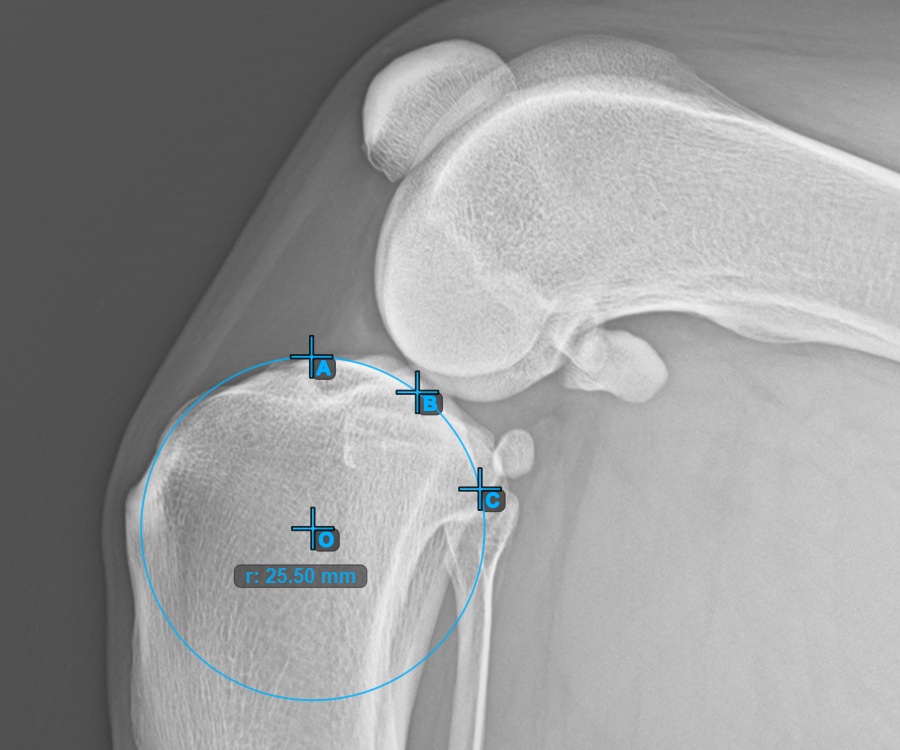

Mark the three points on the main condylus of the tibial bone (Medialis Tibialis). Regardless of the order, make sure to mark the most cranial point, the most caudal point and the midpoint of the Medialis Tibialis. A circle will be automatically constructed based on the three placed points.

The image below represents a typical placement of the three points on the Condylus Medialis Tibialis.